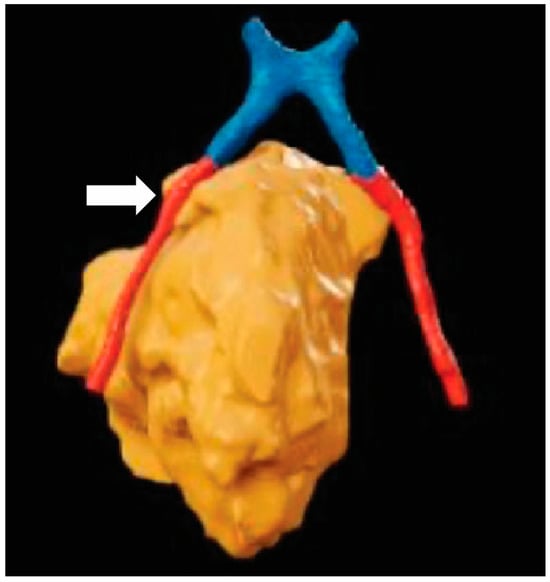

Figure 4.

Surgical planning with XR: A top-down 3-dimensional reconstruction of the optic chiasm (blue), optic nerves (red), and esthesioneuroblastoma (orange). Although the right optic nerve approximates the tumor, there is no direct invasion (white). The reconstructed objects allow for clear visualization of the spatial relationship between anatomical structures that may impact surgical plans.